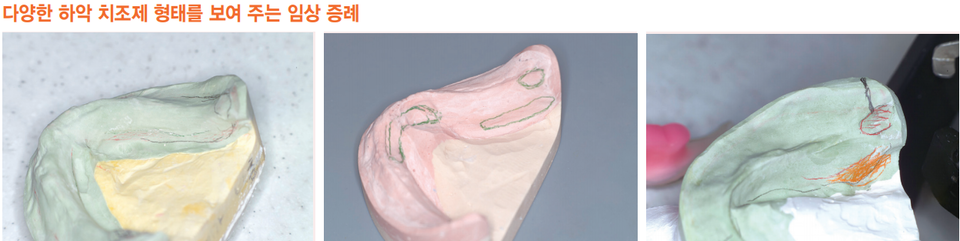

4) 하악 완전의치 완성도를 결정하는 항목 검사

반면에 하악 틀니는 해부학적으로나 기능적으로 많은 한계를 지니고 있다.

설측으로는 혀의 움직임을 반영해 주어야 한다.

협측으로는 구륜근과 저작근의 운동범위가 상악에 비해 2~3배 커서 정확한 인상과 border 결정이 필요하다. 유지력에 중요한 요소인 인상면 면적이 상악보다 작다.

검사항목

① 치조제 형태 (양호, 보통, 불량)

② Retromolar pad 형태 (양호, 보통, 불량)

③ Sublingual fold (양호, 보통, 불량)

④ Mylohyoid fossa 연장 범위 (양호, 보통, 불량)

- 잔존치조제 볼륨이 부족하다.

- Retromolar pad 형태가 왜소하다.

- Retromolar pad 형태의 가장 양호한 상태는 pear shape가 일정한 크기인 경우이다.